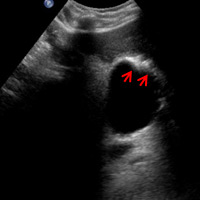

Right upper quadrant ultrasound was performed as the initial diagnostic examination. Transverse gray-scale ultrasound images demonstrated rising nondependent mobile echogenic foci (arrows) within the gallbladder lumen (Figure A). These mobile foci were best appreciated on cine clips and were consistent with effervescent gas bubbles (“champagne sign”). In addition, focal curvilinear echogenicity (arrows) with an associated chaotic display of continuous bright echo tails of variable strength and length (“dirty shadowing”) was noted within the gallbladder wall, confirming the presence of gas (Figure B).

Ultrasound typically demonstrates echogenic foci or focal curvilinear echogenicity with associated dirty shadowing in the gallbladder wall or lumen. A less common but more specific finding is nonshadowing echogenic foci rising from the dependent portion of the gallbladder lumen. CT, however, is the most sensitive and specific imaging modality for identifying gas within the gallbladder lumen or wall.